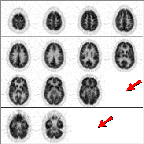

Click on image above to view full-size image.

Another type of artifact is related to the placement of the patient in the scanner. To decide whether the head was tilted in the gantry, first locate the petrous ridges or bones. Normal bone has no FDG metabolism. The arrows point to the site of the petrous ridges (in plane 15 in this scan). The petrous bone appears in a PET brain scan as the absence of activity between the cerebellum and the inferior temporal lobe.

The asymmetry in activity in the plane containing the petrous ridges implies that the head was tilted in this scan. When the head has been positioned properly the absence of activity that is caused by the petrous bones should be symmetrical between the left and right sides. In this example the right petrous bone (on the left side of the image) was in the image plane to a greater degree than was the left petrous bone (on the right).